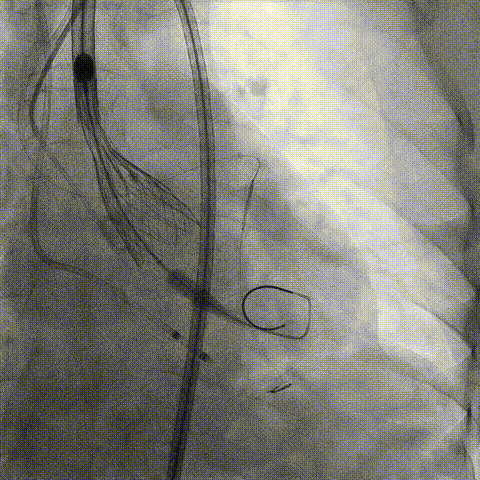

冠脉造影

手术策略和器械选择

预置Telescope™导引延长导管及导丝保护左冠,

18mm球囊预扩张再次评估冠脉闭塞风险。

介入经过及结果

Telescope™+Runthrough

18mm*40mm 预扩张

预埋 Resolute Integrity 3.5*26mm

再次评估左冠开口

第一次释放

再次评估左冠开口,考虑调整瓣膜深度

回收后调整深度,再次释放

评估左冠开口

左冠开口切线位造影

决定左冠烟囱支架保护冠脉

调整支架位置

释放冠脉支架

释放瓣膜

造影评估

支架内后扩张

根部造影